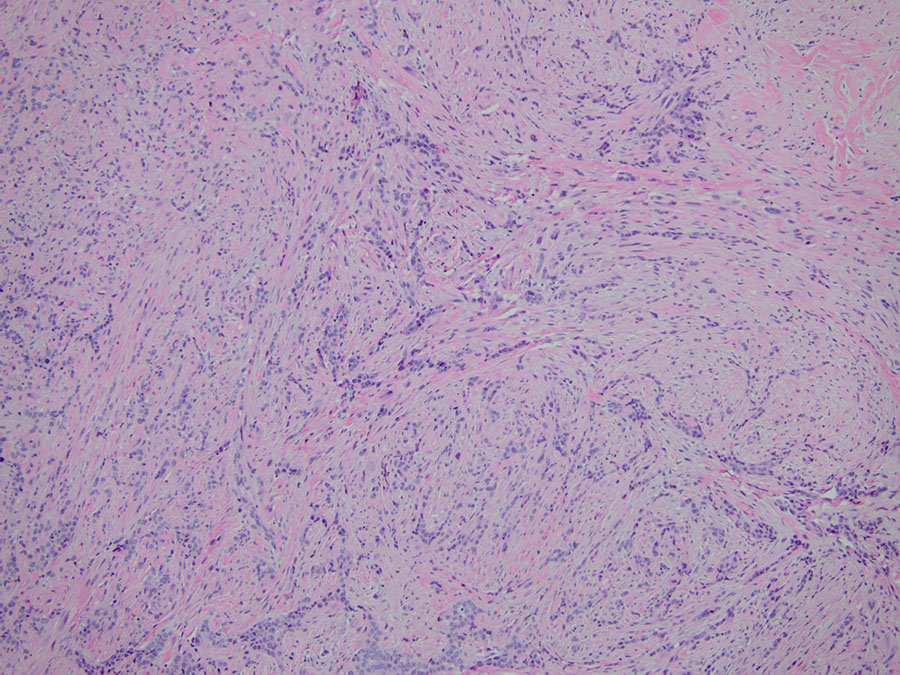

A right video-assisted thoracoscopy was performed and two chest wall biopsies were taken. Fragments of tan-white soft tissue were received, measuring up to 1.8cm in aggregate. Upon histologic evaluation, low-power magnification (2X) revealed a neoplasm with biphasic morphology (Figure 1). Sheets of epithelioid cells were noted within a background of dense fibrosis. Cytologically, the tumor cells appeared monotonous, showing round nuclei with prominent nucleoli. Mitotic figures were inconspicuous (Figure 2). Atypical spindled to ovoid tumor cells were noted in streaming fascicles within dense hyalinized fibrous stroma (Figure 3). The interface of these two patterns is seen in Figure 4. Focal invasion into chest wall fat is noted (Figure 5). The diagnosis was confirmed with positive stains including D2-40, WT-1, calretinin, and pancytokeratin (Figures 6-9). The tumor cells were negative for TTF-1, p40, CEA and CD15.